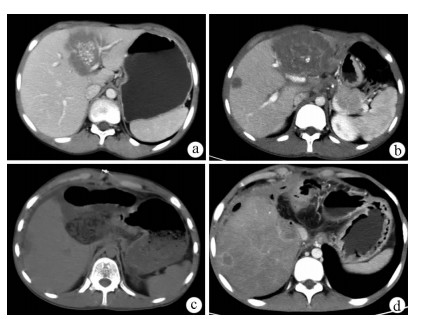

Jaundice and portal hypertension caused by hepatic epithelioid hemangioendothelioma: A case report

Ruihua ZHANG, Tingting QIN, Yueming SHAO, Yu ZHANG, Yang WANG, Xiaoyu WEN

2021, 37(7): 1662-1664. DOI: 10.3969/j.issn.1001-5256.2021.07.036

Abstract(984) HTML (197) PDF (2873KB)(66)

Abstract: